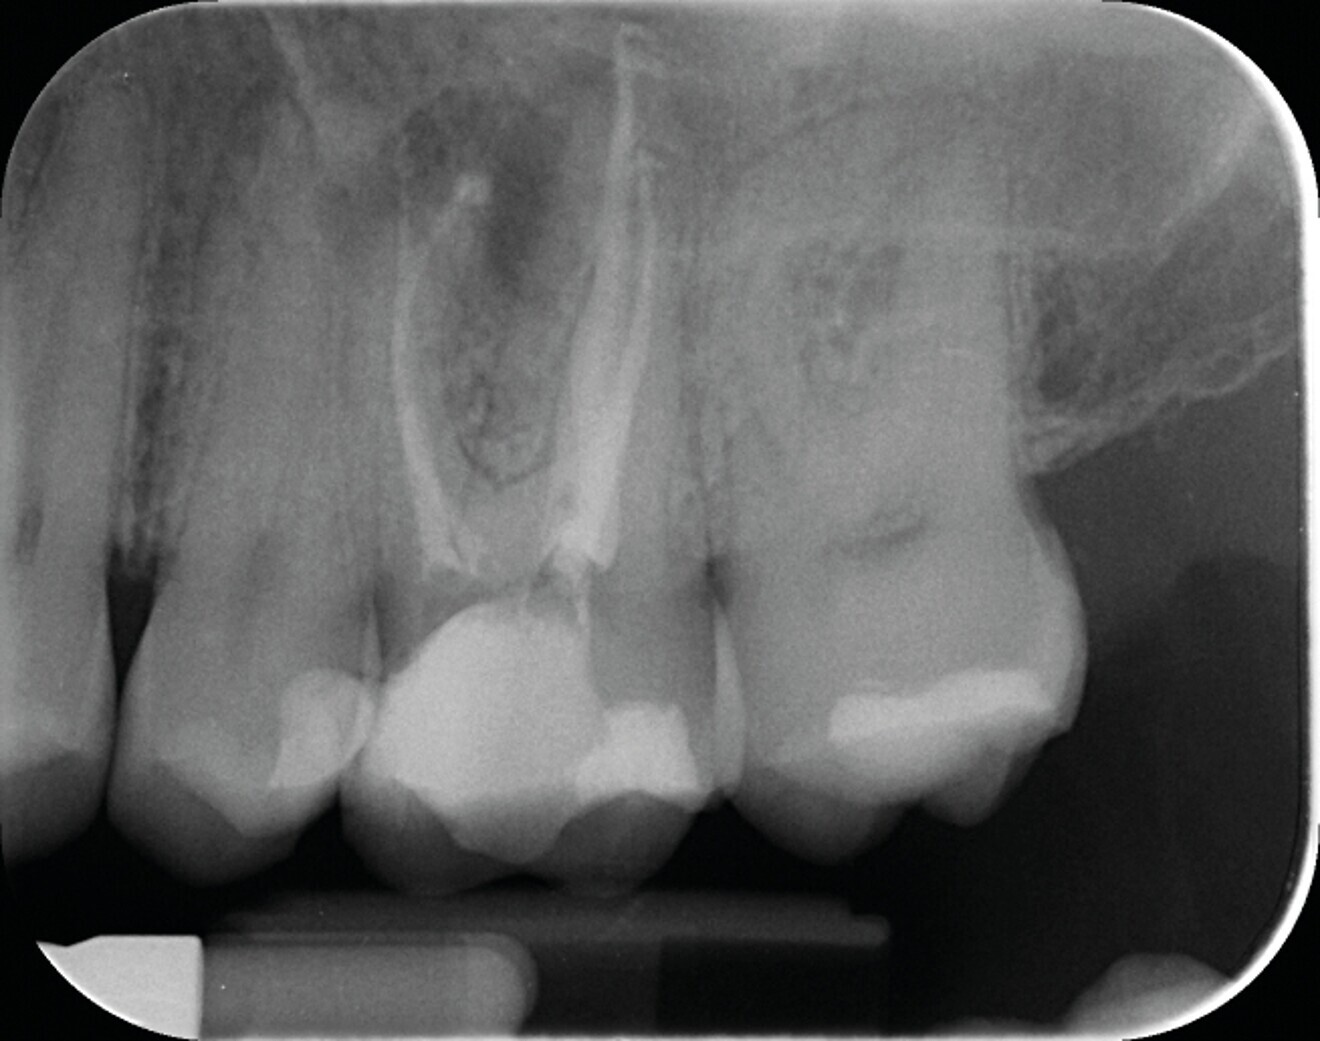

Avec la désinfection et l’obturation du système canalaire, nous ne faisons que rétablir un contexte biologique favorable à la cicatrisation parodontale et à la régénération osseuse (Figs. 1a–c).

Fig. 1a : Radiographie pré-opératoire d’une molaire maxillaire (16) présentant une lésion apicale sur la racine mésio vestibulaire. Le retraitement a consisté à éliminer le matériau présent dans les canaux, récupérer la perméabilité du canal de la racine MV et gérer la fausse route faite lors du traitement précédent.

Fig.1b : La radiographie post-opératoire objective une atteinte des objectifs techniques (obturation Bioroot RCS (Septodont).

Fig. 1c : La radiographie de contrôle à un an, confirme l’efficacité du traitement par la régénération osseuse.